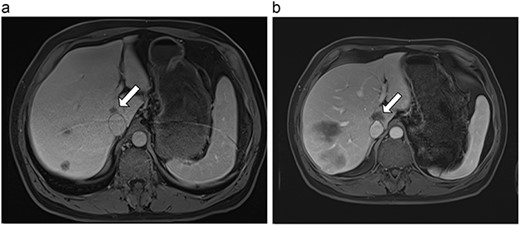

| 4 (6a,b) | 51, M | Colon adenocarcinoma | 6 cycles FOLFOX | 4 | Laparoscopic microwave ablation | 14 | 23.8 | 9.8 | 13 | Yes |

(a) Pre-ablation MRI demonstrating 14 mm lesion in caudate lobe of liver. (b) Post-ablation MRI (23 days postoperatively) demonstrating 23.8 mm complete ablation of caudate lesion.